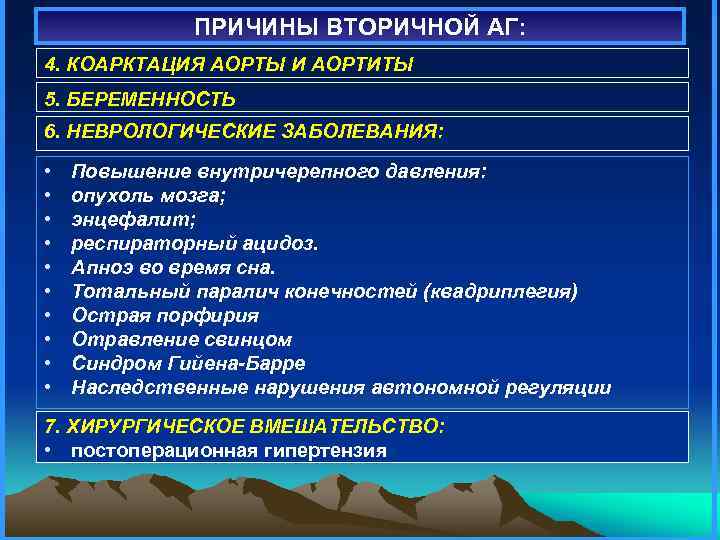

ПРИЧИНЫ ВТОРИЧНОЙ АГ: 4. КОАРКТАЦИЯ АОРТЫ И АОРТИТЫ 5. БЕРЕМЕННОСТЬ 6. НЕВРОЛОГИЧЕСКИЕ ЗАБОЛЕВАНИЯ: • • • Повышение внутричерепного давления: опухоль мозга; энцефалит; респираторный ацидоз. Апноэ во время сна. Тотальный паралич конечностей (квадриплегия) Острая порфирия Отравление свинцом Синдром Гийена-Барре Наследственные нарушения автономной регуляции 7. ХИРУРГИЧЕСКОЕ ВМЕШАТЕЛЬСТВО: • постоперационная гипертензия

ПРИЧИНЫ ВТОРИЧНОЙ АГ: 4. КОАРКТАЦИЯ АОРТЫ И АОРТИТЫ 5. БЕРЕМЕННОСТЬ 6. НЕВРОЛОГИЧЕСКИЕ ЗАБОЛЕВАНИЯ: • • • Повышение внутричерепного давления: опухоль мозга; энцефалит; респираторный ацидоз. Апноэ во время сна. Тотальный паралич конечностей (квадриплегия) Острая порфирия Отравление свинцом Синдром Гийена-Барре Наследственные нарушения автономной регуляции 7. ХИРУРГИЧЕСКОЕ ВМЕШАТЕЛЬСТВО: • постоперационная гипертензия